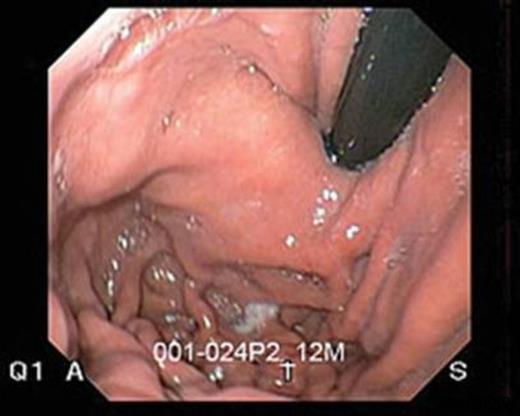

Pre-operative upper endoscopy showed a Hill grade I gastro-esophageal valve, (Fig. 1) grade A esophagitis and normal gastric and duodenal mucosa. Urease test was negative for Helicobacter pylori. Motility study showed only 25% of swallows produced peristaltic wave throughout the esophagus with a mean distal amplitude of 77mmHg. The remaining swallows produced a mixture of low amplitude synchronous waves, partially propagated and non-propagated waves. The lower esophageal sphincter (LES) measured to 3 cm, with 1 cm above the diaphragm. The LES had a mean resting pressure of 9 mmHg, which relaxed with swallowing. A twenty four hour pH study produced a deMeester score of 20.25 (normal range below 14.5).